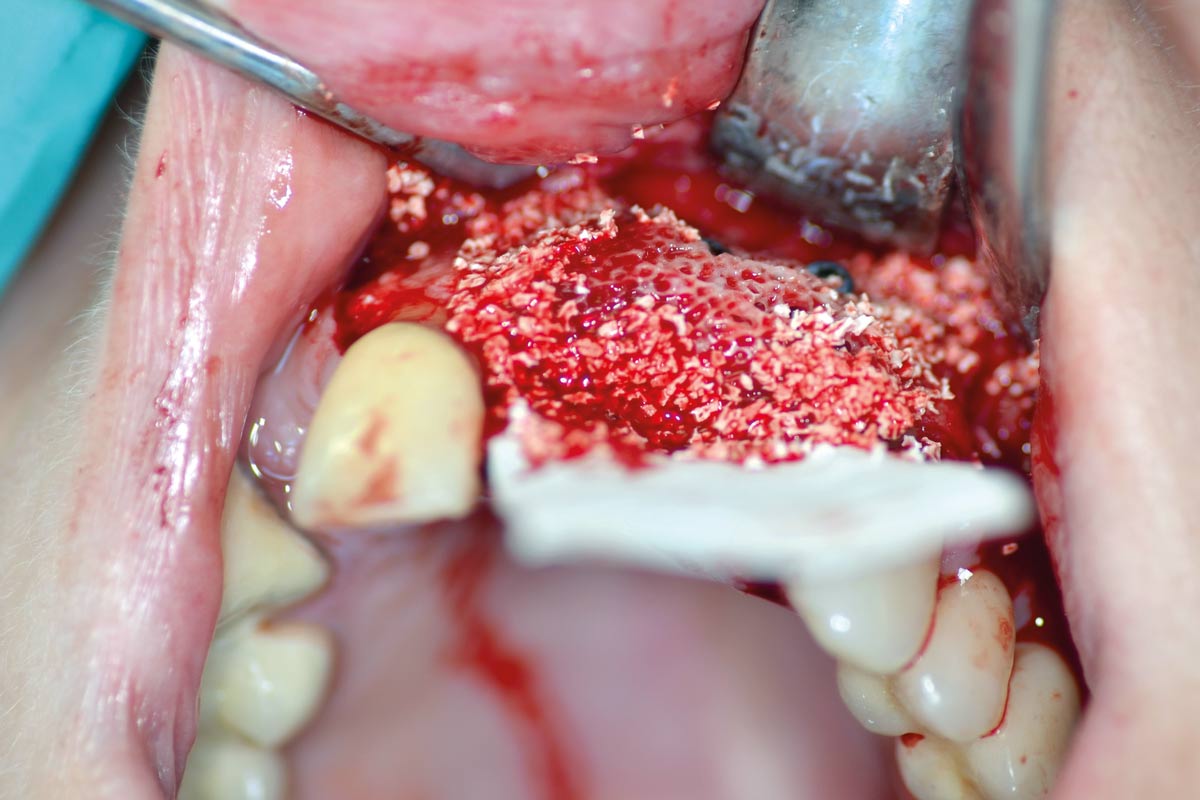

botiss cerabone® & Jason® membrane for horizontal augmentation - Clinical case by Dr. M. Steigmann